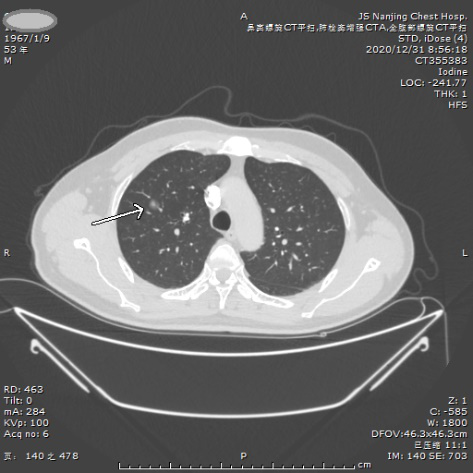

案例一 纯磨玻璃小结节